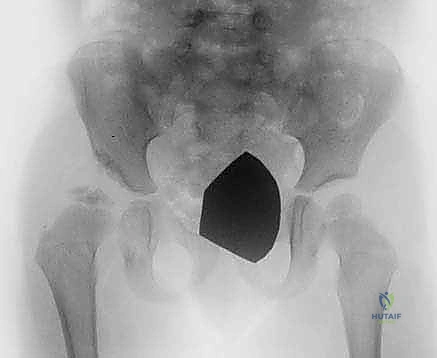

قبل دخول غرفة العمليات، يتم دراسة صور الأشعة السينية والمقطعية (CT Scan) للطفل بدقة، وتحديد زوايا القطع العظمي المطلوبة بالملليمتر.

5. إجراء القطع العظمي (بيمبرتون أو ديجا):

باستخدام أدوات جراحية دقيقة جداً، يتم إجراء القطع العظمي في الحوض وثني سقف الحُق لتغطية رأس الفخذ بالزاوية المثالية التي تم التخطيط لها.

مباشرة بعد العملية، يتم وضع الطفل في الجبس البنطلوني (Spica Cast). هذا الجبس يغطي النصف السفلي من الجسم (من الخصر وحتى الكاحل في الساق المصابة، وإلى الركبة في الساق السليمة). الهدف منه هو الحفاظ على مفصل الورك في الوضعية الصحيحة تماماً حتى تلتئم العظام والأنسجة.